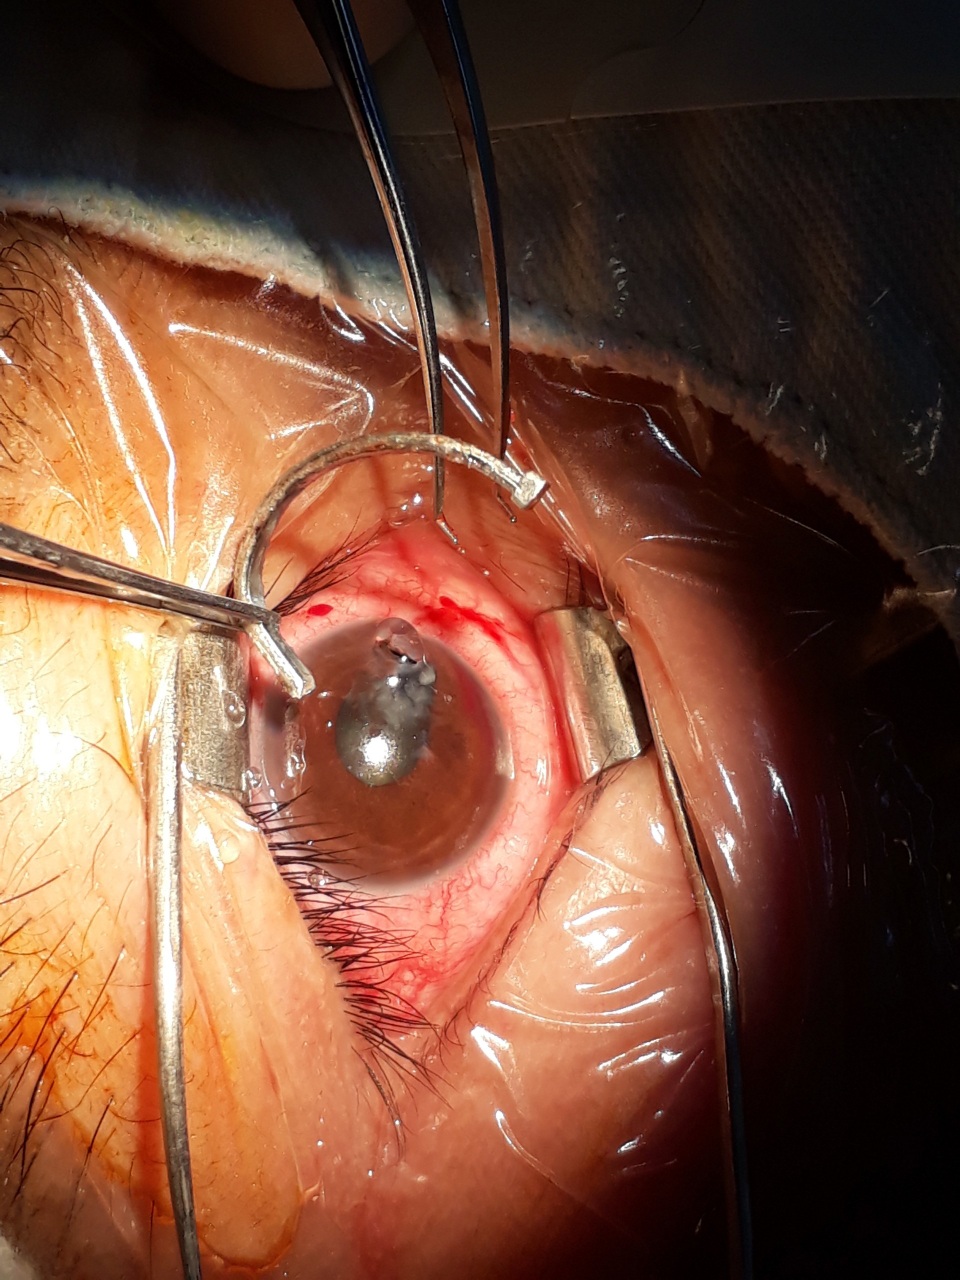

TS.BS Phạm Hồng Vân, kíp trực BV Mắt Trung ương tối 4/1 cho biết, bệnh nhân đến trong tình trạng đinh cắm ngập sâu vào mắt, có thể nhìn thấy phần đuôi của chiếc đinh nằm ngay trên bề mặt mắt.. Ngay lập tức, bệnh nhân được chỉ định chụp X- quang để xác định chấn thương.

Cận cảnh bác sĩ rút đinh 2,5cm ra khỏi mắt bệnh nhân

Trên hình ảnh phim X - quang các bác sĩ thấy một chiếc đinh cong, tiên lượng chưa xuyên thấu nhãn cầu nhưng dị vật này đã đâm xuyên giác mạc, qua mống mắc, xuyên qua thủy tinh thể làm đục vỡ thủy tinh thể. Kíp trực quyết định thực hiện ca phẫu thuật ngay trong đêm để rút dị vật đinh ra khỏi mắt bệnh nhân.

Sau ca phẫu thuật, hiện bệnh nhân đang được theo dõi hồi phục để thay thủy tinh thể.